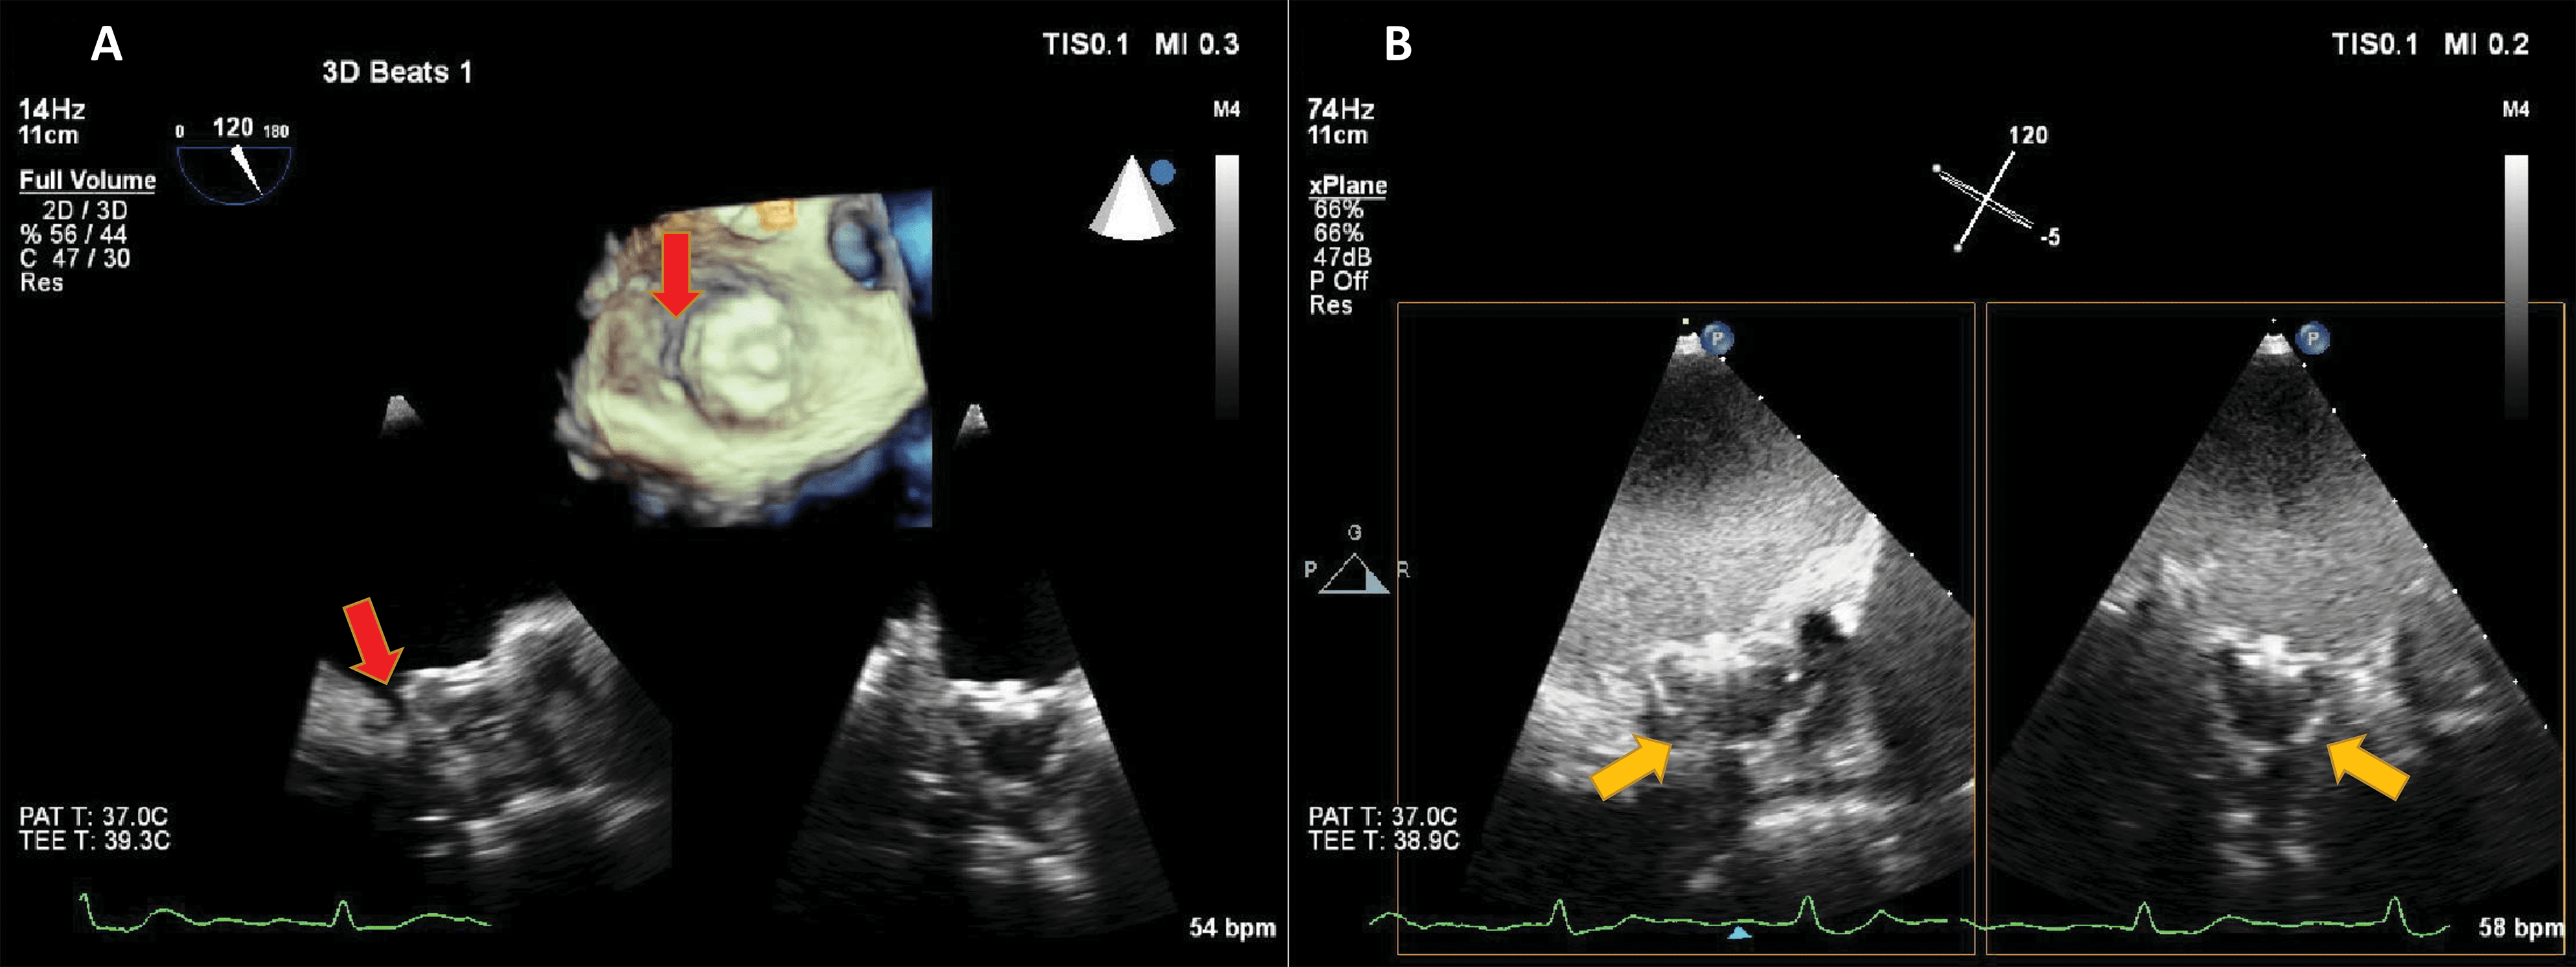

UEA have largely been used in the detection of LV thrombi [76, 77, 78]. This is in fact an application of the LVO method, enhancing the delineation between the wall, cavity and the thrombus mass (Fig. 10, Ref. [79]). However, prognostic implications for small mural thrombi are not clear. Myocardial perfusion detection, as described above, may help to diagnose small intracardiac or even intramural masses, by the presence and the dynamics of the vascularization inside the mass [80]. By adding a quantitative approach, it may even be possible to differentiate not only thrombi from tumors, but also benign from malignant tumors [79] (Fig. 11, Ref. [79]).

Fig. 10.Detection of an apical thrombus in a patient with severely depressed EF. Native images in apical 4 (A) and 2 chambers (B) do not demonstrate the presence of an apical mass. (C) 3D contrast-enhanced echocardiography demonstrating an apical filling defect (thrombus-arrows). (D) Apical 2-chambers 2D contrast-enhanced image, the thrombus is present in the apical LV. Images modified with permission from Strachinaru et al. [79].